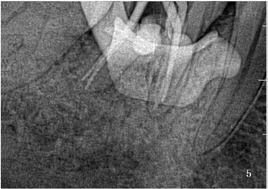

排除禁忌证后于2021年3月16日行"远中髓室底及近中根管口穿髓孔修补术+根管预备"治疗。首诊治疗过程为46上橡皮障,去净龋坏组织,充分暴露髓腔,行1%次氯酸钠溶液冲洗+超声荡洗髓室底穿孔区,直至穿孔区无明显活动性出血。使用根尖定位仪测得MB、ML、DB、DL根管长度均为16mm。使用iRoot-BP+富士Ⅸ玻璃离子分别修补远中髓室底穿孔区(图3a、图3b)及近中根管口穿孔区(图4a、图4b),待修补材料固化后行10#、15#C锉疏通MB、ML、DB、DL根管,17%EDTA凝胶+镍钛锉Protaper Next机扩至X2,试尖合适(图5),40#吸潮纸尖干燥,根管内封氢氧化钙糊剂,ceivitron暂封。(操作视频于附件中)